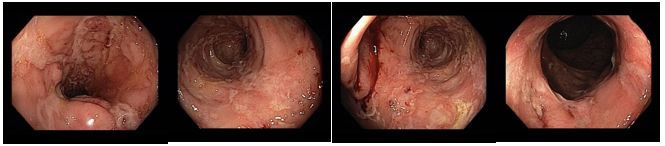

Koloskopie 2018/8: Mírné floridní zánětlivé změny (ložiskové zarudnutí a setřelá podslizniční cévní kresba, aftoidní léze) v blízkosti hepatálního ohbí v colon ascendens a v sigmatu. Pozánětlivé změny (jizvy po serpiginózních ulcerací v příčném a levém tračníku, vlevo i pozánětlivá trabekulizace. Normální terminální ileum.

Histologie: Mikroskopický nález je kompatibilní s klinickou diagnózou idiopatického střevního zánětu, resp. Crohnovy choroby, přičemž je patrna aktivita onemocnění. Dysplastické změny neprokázány.